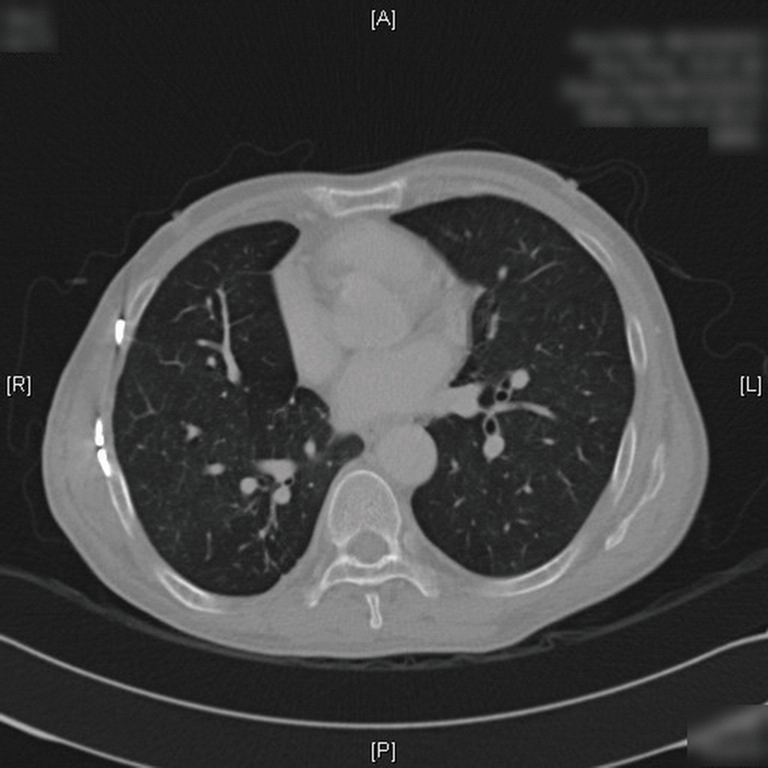

From pulmonarychronicles.com

Medical image Titanium Plate In Chest bilateral sternoclavicular joints were accumulated in the manubrium. two recent studies suggest that titanium plate fixation can provide a primary method for sternotomy closure in patients at risk. in our study, we evaluated the relatively recent method of sternal closure using the sternalock titanium plates in. there is increasing evidence to suggest that rigid plate fixation. Titanium Plate In Chest.